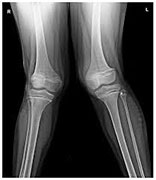

Flat feet can impact the knees by causing the shinbone (tibia) to rotate inward. This inward rotation can shift the kneecap (patella) and patellar tendon slightly inward as well, resulting in a "knock-kneed" appearance. The misalignment doesn’t stop at the knees—it can also affect the hips and even the lower back, leading to more pain and discomfort.